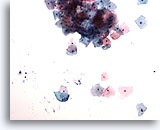

Lubricant C treated vial

…shows the lubricant staining a deep purple and resembling dense mucoid material in appearance. In this instance, the specimen had very scant cellularity and fragments of lubricant obscuring the epithelial cells. The decreased cellularity was most likely the result of excessive lubricant interfering with cell collection during slide preparation.

10x

Lubricant C treated vial

…shows the lubricant staining a deep purple and resembling dense mucoid material in appearance. In this instance, the specimen had very scant cellularity and fragments of lubricant obscuring the epithelial cells. The decreased cellularity was most likely the result of excessive lubricant interfering with cell collection during slide preparation.

10x